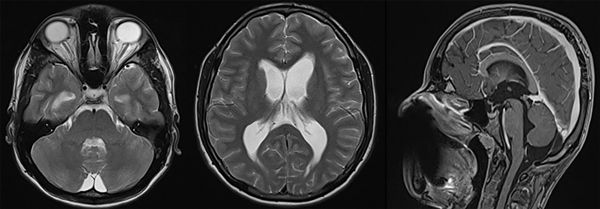

Se evalúan la TAC y la RM de cerebro simple y con contraste sin evidencia de lesiones que condicionen una obstrucción del paso del líquido cefalorraquídeo a través del sistema ventricular; se realizan mediciones con índice de Evans con resultado mayor a 0.3, el diámetro de la vaina del nervio óptico es mayor a 5 mm y presenta edema transependimario (Figura 3), concluyéndo que se trata de una hidrocefalia comunicante con alto riesgo de desarrollo de hipertensión intracraneana, por lo cual el paciente es motivado a cirugía de urgencia para colocación de un sistema de derivación ventriculoperitoneal (Figura 4).

Figura 3. RM de encéfalo, secuencia T2 y con contraste (izquierda a derecha): diámetro de la vaina del nervio óptico mayor a 5 mm, edema transependimario e hidrocefalia.